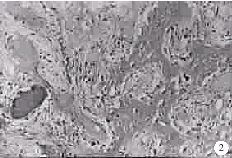

图2 止血成骨胶组术后12周 骨缺损完全由新生骨组织填充 (HE×400)

Fig 2 Hemostatic-osteosis jelly group in 12th week The bone defect were completely filled with the newly formed bone (HE×400)

术后4周,缺损区可见纤维性骨痂出现,内含大量成纤维细胞,间充质细胞及丰富的新生毛细血管,见图1。间充质细胞增殖,转化为骨软骨细胞和成骨细胞,还见少量残存的BMG颗粒,其中央出现“软骨岛”,周边有成团的破骨细胞吞噬其基质;术后8周,间充质细胞明显减少,成骨细胞增生活跃,大量骨细胞出现,新生骨小梁形成,呈网织状结构,植入物已基本吸收,术后12、16周,缺损区完全由新生骨代替,成骨细胞减少,骨细胞增多,骨小梁更趋成熟,骨髓腔及骨髓细胞日趋完善,骨缺损修复完成,见图2。